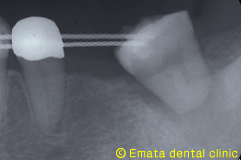

親知らずを移植歯に使用しました。大きさ、根の形態、歯根膜の状態、すべてに適応症の歯です。 |

| 歯牙移植手術 | |